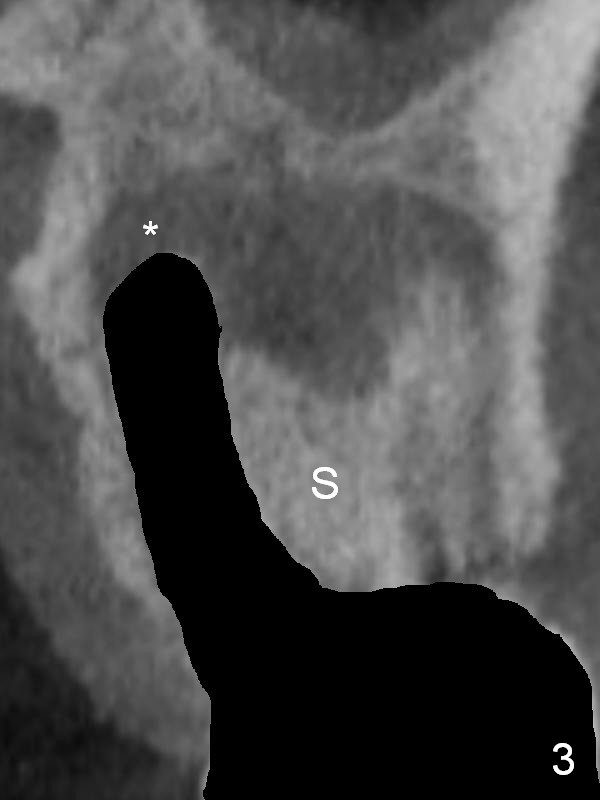

There is purulent discharge from the mesiobuccal fistula (Fig.1 <) during the tooth #14 extraction. Fig.2 is a coronal section of CBCT of the affected tooth showing a large apical lesion (*). When the tooth is removed (Fig.3), limited amount of granulation tissue is removed apical to the palatal root (P in Fig.2). The granulation tissue (Fig.4 red area) above the septum (Fig.3 S) is thoroughly extirpated when the septum is removed (Fig.5 black area).